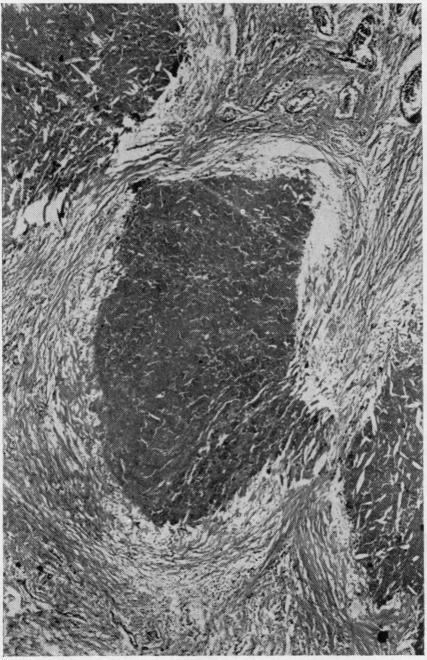

Stages in the retrogression of testicular seminoma are described. Eosinophilic necrosis fringed by palisaded histiocytes may be followed by fibrous replacement. Oxidation of unsaturated phospholipids in necrotic tumour may lead to deposition of lipofuscin around the lesion. Search for partially or completely scarred lesions is essential before contemplating a diagnosis of primary retroperitoneal seminoma. Retrogressed seminoma can often be distinguished from retrogressed teratoid tumours. Apparently paradoxical teratoid metastases in association with a testicular seminoma are explained on the basis of misinterpreted retrogressed teratoid tumours in association with the seminoma. Inguinal node metastases from testicular seminoma may be the result of abnormal lymphatic drainage following previous scrotal operations, testicular torsion etc.

描述了睾丸精原细胞瘤消退的各个阶段。嗜酸性坏死周围有栅栏状组织细胞包绕,随后可能被纤维组织替代。坏死肿瘤中不饱和磷脂的氧化可能导致脂褐素在病变周围沉积。在考虑诊断原发性腹膜后精原细胞瘤之前,寻找部分或完全瘢痕化的病变至关重要。消退的精原细胞瘤通常可与消退的类畸胎瘤相鉴别。与睾丸精原细胞瘤相关的明显矛盾的类畸胎瘤转移,是基于与精原细胞瘤相关的类畸胎瘤被误判为消退而得到解释。睾丸精原细胞瘤的腹股沟淋巴结转移可能是先前阴囊手术、睾丸扭转等导致异常淋巴引流的结果。